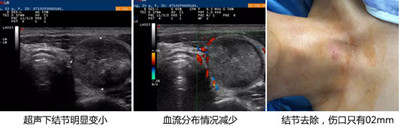

国家专利技术:根据患者结节的大小、边缘情况、内部血流情况等,在美国GE四维彩超下,将甲状腺结节放大数十倍,即使针尖大小的潜在结节也可清晰呈现,通过微创介入,一次清除。不开刀、不住院、不用终身服药,治后贴个创口贴即可出院。

准确锁定病灶:通过美国GE四维彩超,准确锁定病灶,精确控制病灶范围、大小。

微创介入,一次性消除结节:超声引导,局部麻醉后将消融针穿刺入病灶组织进行消融,使其病变部位发生热固化,一次性将肿块细胞的活性完全消失。

直击病灶,彻底治好:消融温度达70°C自动中止电流,保证病变组织坏死且不损伤正常细胞,又能防止灼伤皮肤、气管。

1、见效快:当天结节消失,治疗7天,针孔淡化,1个月后,无疤无痕

2、不开刀,创伤小:不损伤周围血管、气管,伤口只有0.2mm,术后贴个创口贴。